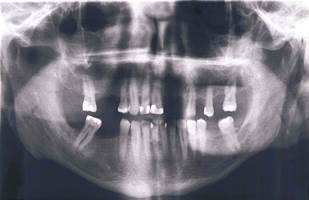

El paciente refiere no presentar hábitos tóxicos como tabaquismo o ingesta de alcohol. Este paciente fue clasificado como ASA II. A la exploración extraoral se evidenció paciente normocefálico, implantación capilar androide con tercios proporcionales, piel perioral sana y perfil recto, sin alteraciones relevantes. A la exploración intraoral presentaba ausencia de órganos dentarios 21, 22, 23, 24, 26, 28, 15, 16, 18, 45, 46, 48, 36, 38 (Figura 1).

Atrición dental en órganos anterosuperiores y anteroinferiores (Figura 2), al examen periodontal presentó recesiones gingivales en órganos dentarios 14, 17, 23, 25, 27, 33, 35, 41, 44, 47, sangrado en 34, 27 y 13, no se evidenciaron bolsas periodontales, lesiones de furca ni movilidad. Se procedió a realizar montaje en articulador con el fin de analizar oclusión del paciente y realizar un plan de tratamiento el cual consistió en rehabilitación con prótesis fija completa superior e implantes para reemplazar órganos dentarios 36 y 46.

Para la colocación de implantes en sector inferior, con el fin de reemplazar los órganos dentarios 36, 45 y 46, se inició realizando un TAC (tomografía axial computarizada), para evaluar el espesor y densidad ósea; el examen arrojó que existía un buen soporte de hueso para los implantes. Antes de la cirugía se realizó interconsulta con el médico tratante de la patología de base y se suspendió el clopidrogel 75 mg cuatro días antes y se mantuvo el Adiro 100 mg. El procedimiento se inició en la hemiarcada inferior izquierda para reemplazar órgano dentario 36, colocándose anestesia local (mepivacaina® al 3% sin vasoconstrictor), se realizó incisión supracrestal e intrasulcular con bisturí convencional (Bard Parker® N°3, hoja N° 15) para colocar implante STRAUMAN stándar plus de 4,1mm x 10mm de longitud roxolid SLActive; con ayuda de una guía quirúrgica, se inició la perforación con fresa de diamante redonda de 2,3 mm, luego con fresa piloto de 1,2 mm, luego se utilizó la fresa helicoidal 3,5 mm y por último la fresa de perfil, todas a 10 mm de longitud. No se presentó abundante sangrado durante el procedimiento. Se colocó sutura de dos puntos simples nylon negro monofilamento 4/0 (Ethilon™) no reabsorbibles, la cual se retiró a la semana sin complicaciones (Figura 4).